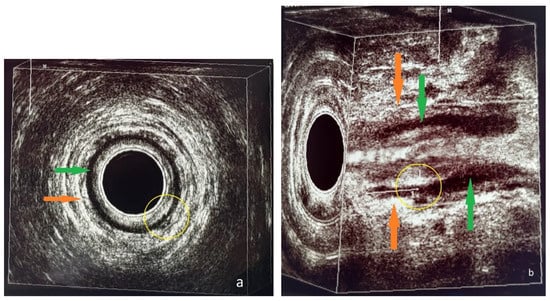

The 3D-EAUS was performed by a colorectal surgeon certified in endoanal imaging with 10 years of experience who was blinded to the results of the MRI. A colorectal surgeon trainee in endoanal imaging participated in the 3D-EAUS procedure. Hydrogen peroxide enhancement was not applied. A perianal fistula was recognized as a hypoechoic tract that penetrated the anal sphincters or the perianal anatomical spaces and could branch into secondary extensions. The internal orifice of the fistula was shown to disrupt the IAS, according to Cho’s three criteria [11]. A perianal abscess was visualized as a mixed hypo- and hyperechoic region with debris and gas bubbles (Figure 3 and Figure 4).

Figure 4. Patient no. 2; preoperative 3D-EAUS. (a) Axial plane. Intersphincteric perianal fistula with concomitant abscess cavity at 11 o’clock in the anal canal (yellow circle). (b) Sagittal plane, tridimensional reconstruction. Submucosal perianal fistula on the posterior wall (6 o’clock) of the anal canal (yellow circle).